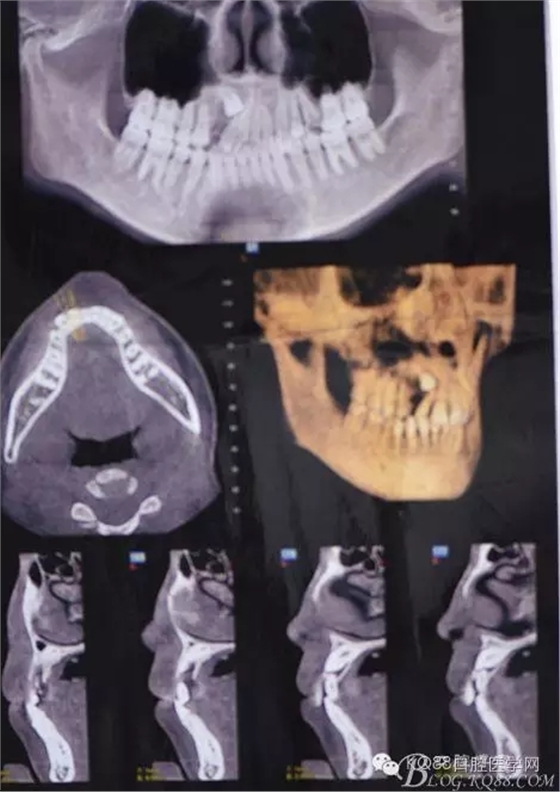

患者、女、高xx、17歲,主訴:外院轉(zhuǎn)診要求拔除埋伏牙。專科檢查:53殘根滯留、牙根斷面位于齦下,cbct檢查:13高位埋伏,牙冠壓迫12牙根的遠中面,牙根未見吸收,經(jīng)我院正畸科會診,建議拔除13、53,然后再正畸治療?;颊咄庵委煼桨?,術(shù)前簽知情同意書。 拔牙過程: 圖1.術(shù)前的cbct檢查:13位于12遠中根尖區(qū),13牙根接近上頜竇、53牙根滯留。 圖2.口內(nèi)觀:53滯留、牙根斷面位于齦下,12牙冠唇傾。 圖3.合面觀:12畸形舌側(cè)窩、腭側(cè)沒有明顯隆起 圖4.首先拔除53,然后在23唇側(cè)區(qū)域的前庭溝處的黏膜做弧形切口 圖5. 翻瓣 圖6.去骨 圖7.暴露出13牙冠 圖8.高速渦輪機分牙、目的是盡量少去骨。 圖9. 從頸部截分13 圖10. 13牙冠頸部分牙情況 圖11.再把牙冠分成近中、遠中兩部分。 圖12.取出13牙冠 圖14.取出13牙根 圖15.取出的13的牙根 圖16.拔除13牙后形成的拔牙創(chuàng)。 圖17.拔除的13. 圖18.縫合